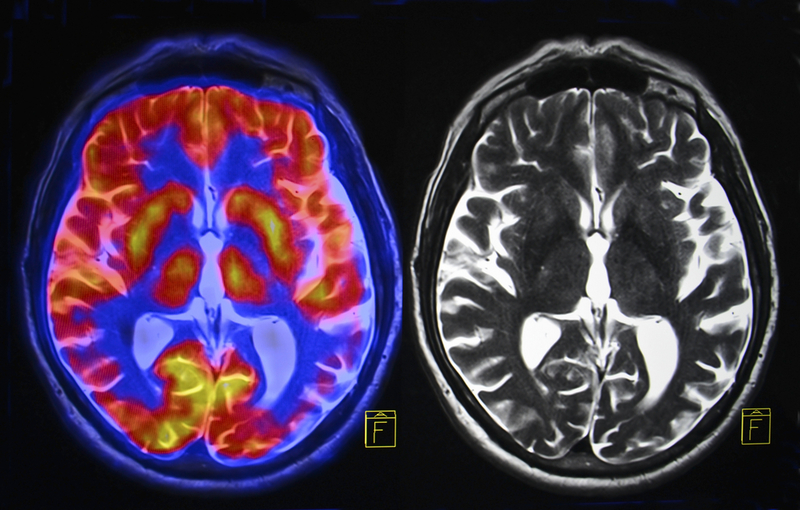

Yale researchers have tested a new method for directly measuring synaptic loss in individuals with Alzheimer’s disease. The method, which uses PET imaging technology to scan for a specific protein in the brain linked to synapses, has the potential to accelerate research for new Alzheimer’s treatments, the researchers said.

To quantify synaptic loss, the research team used a specific radioactive chemical, [11C]UCB-J, that binds with a protein, the SV2A, that is present in nearly all synapses. The researchers recruited 21 older adults with either early Alzheimer’s disease or normal cognitive ability. Each was injected with [11C]UCB-J and then scanned with high-resolution PET technology. The scans allowed the researchers to visualize synaptic “density” in different regions of the brain.

The researchers analyzed the scans, as well as results from MRIs and cognitive evaluations for both groups. Compared to individuals with normal cognition, the participants with Alzheimer’s disease had a 41% reduction in the SV2A marker in an area of the brain associated with memory.

“We found that in early Alzheimer’s disease, there is loss of synaptic density in the region of the hippocampus,” said first author Ming-Kai Chen, MD, associate professor of radiology and biomedical imaging, and co-medical director of the PET Center.

The findings show that the noninvasive PET test can provide a direct measure of synaptic loss in adults with even mild cognitive impairment. “With this new biomarker, PET imaging for SV2A, we can measure synaptic density in the living human brain,” Chen noted.